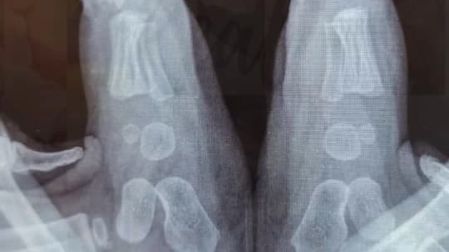

Los pies de los recién nacidos están compuestos, en su mayoría, por cartílago. Es un tejido blando, flexible y en constante crecimiento, que más adelante se transformará en hueso a través de un proceso llamado osificación. Este proceso no se completa sino hasta bien entrada la infancia, incluso hacia los 6 o 7 años en algunas estructuras del pie. Por ello, la exposición temprana a calzado rígido o ajustado puede alterar la alineación, la movilidad y el desarrollo natural del pie infantil.

Una radiografía que se ha hecho viral recientemente muestra los pies de un bebé de 10 meses. En ella se aprecian claramente las zonas de cartílago aún no osificadas, lo que evidencia la fragilidad de estas estructuras en formación. Este tipo de imágenes médicas ayudan a visualizar por qué el uso temprano del calzado puede ser contraproducente: los huesos aún no se han formado del todo y son altamente susceptibles a deformaciones si se aplican presiones externas innecesarias.